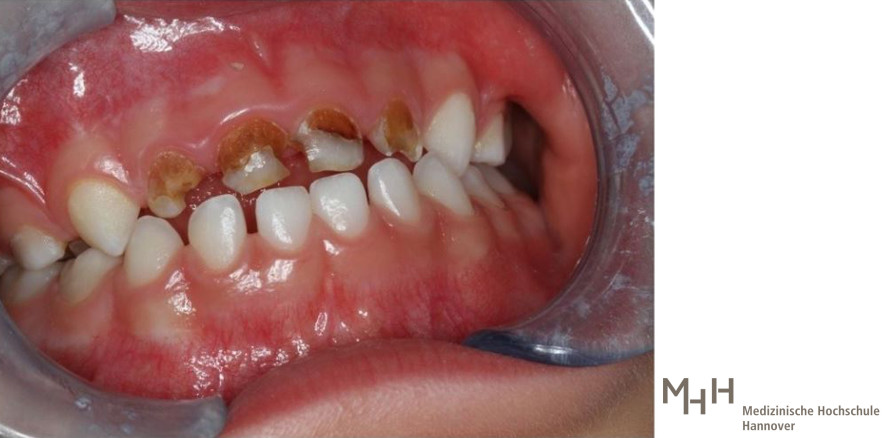

Um die Zahngesundheit der Kinder in Deutschland scheint es nicht gut bestellt: Der Zahnreport 2020 der Krankenkasse Barmer, der sich auf Daten aus dem Jahr 2018 beruft – schlägt Alarm und verweist auf große Defizite bei der Zahnpflege unserer Kleinsten. Demnach wurden 2018 33 Prozent der Zwölfjährigen, also rund 240.000 Kinder, wegen Karies behandelt. Vor allem im Milchgebiss sei Karies weit verbreitet – das hat Folgen. Den Zahnärzten an der MHH bereitet außerdem die Zunahme einer rätselhaften Krankheit Sorgen. Kinderzahnarzt Dr. Alexander Rahman von der MHH-Klinik für Zahnerhaltung, Parodontologie und Präventive Zahnheilkunde erklärt die Hintergründe.

Ja, und zwar ist das die Molarenen-Inzisiven-Hypermineralisation (MIH), umgangssprachlich Kreidezähne genannt. Das ist eine Fehlfunktion, die den Zahnschmelz so sehr schädigt, dass er weich wird. Dadurch werden die Zähne porös und sehr empfindlich gegenüber Kälte und Hitze. Vor Kurzem hatte ich zum Beispiel einen Jungen, der kein kaltes Wasser trinken konnte. Die mangelhafte Schutzschicht macht den Zahn zudem anfälliger für Karies. Betroffen sind die bleibenden Backenzähne sowie die Frontzähne, die sich weiß-gelblich oder gelb-bräunlich verfärben. Es gibt aber auch schon vermehrt Fälle, bei denen es bereits an den Milchzähnen aufgetreten ist. Laut einer deutschlandweiten Studie sind bereits knapp 30 Prozent der Zwölfjährigen davon betroffen.

So einfach ist das nicht. Wenn Sie einmal Karies haben, dann bleiben die Bakterien da. Wenn Sie Karies an einem Milchzahn haben, kann sich das auf den darunter liegenden Zahn auswirken, sodass dieser auch von den Bakterien angegriffen wird. Auch wenn der Milchzahn so stark entzündet ist, dass sich ein Abszess bildet, kann sich das auf den Schmelz des folgenden Zahns negativ auswirken. Dieser wird dann bräunlich verfärbt und ist empfindlicher für Karies.